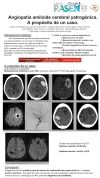

Angiopatía amiloide inflamatoria pseudotumoral con respuesta favorable a corticoterapia